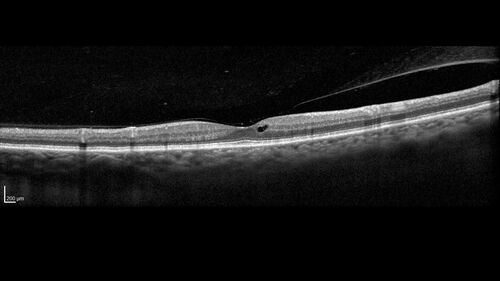

Choroidal Melanocystosis

65 year old female with normal vision.